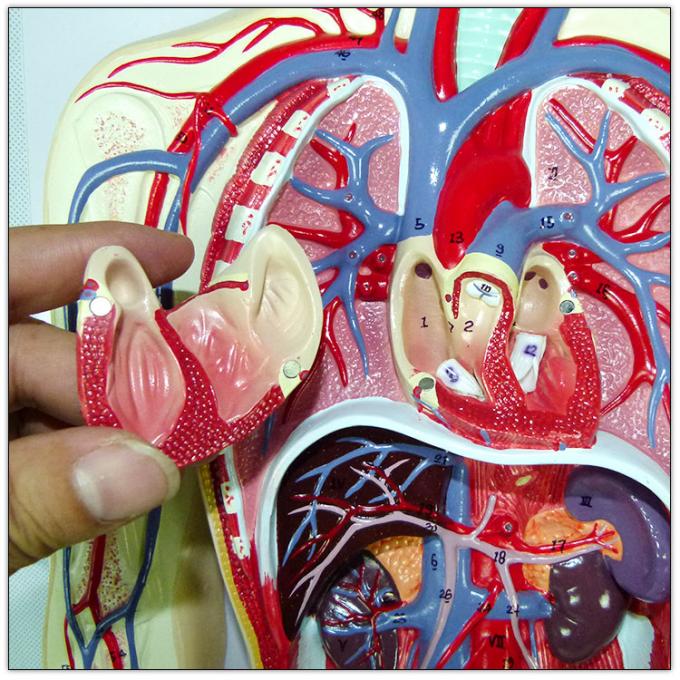

วันหัวใจโลก | Oldeenglishconsortium รูปแบบการสอนแบบระบบไหลเวียนโลหิตของมนุษย์ / การสอนแบบจำลองการไหลเวียนโลหิต

รูปแบบการสอนแบบระบบไหลเวียนโลหิตของมนุษย์ / การสอนแบบจำลองการไหลเวียนโลหิต รูปแบบการสอนแบบระบบไหลเวียนโลหิตของมนุษย์ / การสอนแบบจำลองการไหลเวียนโลหิต

รูปแบบการสอนแบบระบบไหลเวียนโลหิตของมนุษย์ / การสอนแบบจำลองการไหลเวียนโลหิต อวัยวะภายในและระบบไหลเวียนโลหิตของหญิงสาว ภาพประกอบสต็อก – ดาวน์โหลดรูป …

รูปแบบการสอนแบบระบบไหลเวียนโลหิตของมนุษย์ / การสอนแบบจำลองการไหลเวียนโลหิต รูปแบบการสอนแบบระบบไหลเวียนโลหิตของมนุษย์ / การสอนแบบจำลองการไหลเวียนโลหิต

รูปแบบการสอนแบบระบบไหลเวียนโลหิตของมนุษย์ / การสอนแบบจำลองการไหลเวียนโลหิต ฟิตเพิ่มเกรด ชีวะ ม.ปลาย – หัวใจเเละระบบหมุนเวียนเลือด – Dek-D’s School

แบบจำลองระบบหมุนเวียนโลหิตของมนุษย์ – EnterCenterShop ระบบหมุนเวียนโลหิต

แสดงแบบจำลองกายวิภาคศาสตร์การไหลเวียนโลหิตรวมถึงระบบหัวใจและหลอดเลือด … โปสเตอร์เรื่องระบบไหลเวียนโลหิต โปสเตอร์ภาพประกอบการศึกษา โปสเตอร์การ …